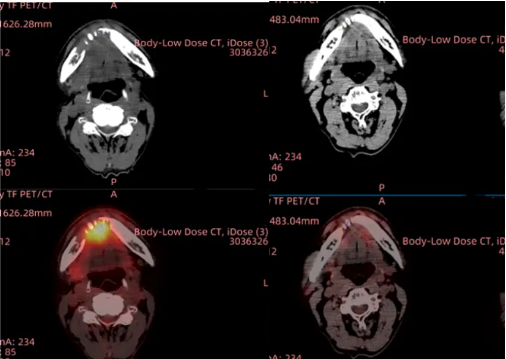

头颈癌:晚期头颈鳞癌9周肿瘤清零,中国TIL疗法改写癌症终局

当所有治疗方案失效,一位经历7年抗癌斗争的头颈鳞癌晚期患者在回输自体肿瘤浸润淋巴细胞后9周实现所有病灶完全消失,TIL疗法让他重获新生!这不仅是中国实体瘤免疫治疗的重大突破,更为全球每年新增70万头颈癌患者点燃了希望之火。